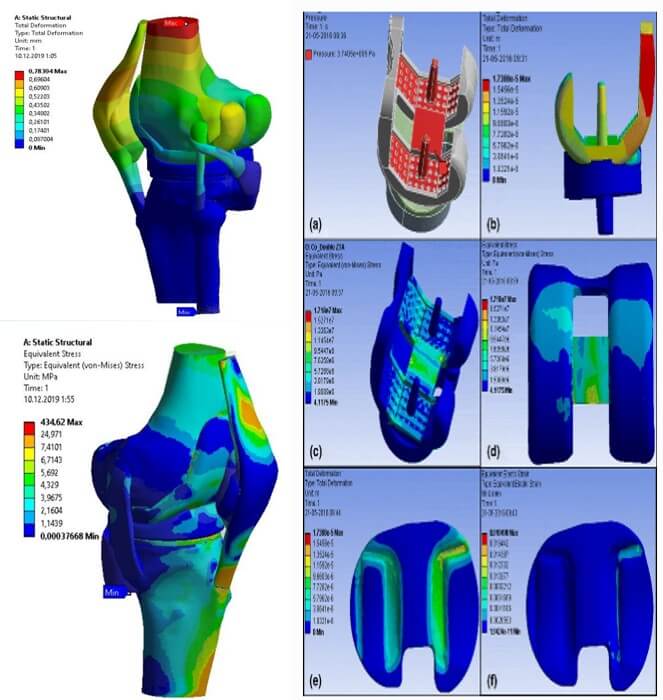

- На сьогодні, завдяки сучасним компьютерним технологіям ми маємо можливість виконання розрахунку навантажень та деформацій у протезованому суглобі в програмному середовищі з метою розробки та створення віртуальних моделей анатомічних умов оперативних втручань, підготовка шаблонів для виконань остеотомій та резекцій, З D друк макетів. Проектування навігаційних систем.

- Математичне та натурне моделювання змін пружніх деформацій в протезованому суглобі, компонентах ендопротеза, кістках суглоба з дефектами у програмному середовищі SolidWorks, або інш., з метою розробки технології заміщення кісткових дефектів, розробка ревізійного ендопротеза суглоба з індивідуальними 3-D друкованими аргументами, заміщення пухлинних дефектів, та дефектів військового часу.

МОДЕЛЮВАННЯ НАВАНТАЖЕНЬ В ПРОТЕЗОВАНОМУ КОЛІННОМУ СУГЛОБІ

- біомедичні технологіі, математичне та анатомічне моделювання змін пружніх деформацій в протезованому суглобі, компонентах ендопротеза, кістках, суглобах з дефектами, у програмному середовищі ansys, solidworks, та інш. дозволяє раціонально планувати та успішно виконувати найскдніші оперативні втручання.

- біомедична інженерія за допомогою проектування індивідуальних навігаційних систем, дозволяє досягти ідеального відновлення біомеханіки протезованого суглоба, дозволяє зменшує навантаження на кістку, тобто досягти успішного довготривалого результату лікування хворих з дефектами кісткової тканини.